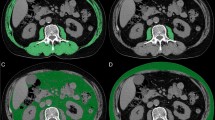

VA activates SIRT3 and mitochondrial dynamics in TA of a mouse model of cancer-induced cachexia

Dysregulation in mitochondrial function, including mitochondrial dynamics, biogenesis, and oxidative metabolism is being extensively studied in cancer cachexia. In particular, decreased expression of mitochondrial fusion-related proteins was observed in skeletal muscle during cancer cachexia11. We also observed that the expression of MFN1, a mitochondrial fusion-related factor, was decreased in the TA tissue of cancer-induced cachectic mice (Fig. 4A). Recent studies suggest the involvement and participation of SIRTs in the regulation of mitochondrial dynamics14,15,16. We thus next evaluated the involvement of SIRT3 by measuring the VA-induced regulation of SIRT3. As expected, the SIRT3 level was decreased in the TA tissue from the CT26 mice, and the SIRT3 expression was recovered to the normal level along with MFN1 by VA treatment (Fig. 4A). Additionally, by a western blot analysis, we confirmed decreased MFN1, SIRT3, and PGC1α expression in TA tissue of CT26 mice. Again, these markers were reversed to normal levels in the TA tissue of VA-treated CT26 mice. However, the expression of SIRT1 and DRP1, which were expected to change along with changes in SIRT3 and MFN1, did not differ among all groups (Fig. 4B). The expression of OXPHOS complexes is associated with mitochondrial function. We see an increase of OXPHOS in the CT26 group, however VA treatment significantly decreased the protein levels of OXPHOS complexes (Fig. 4C).

A TA was immunostained with antibodies for SIRT3 and MFN1 and counter-stained with DAPI for visualization of the cell nucleus (magnification ×400). Fluorescence intensity was quantified using ImageJ software and presented as bar graphs. B Protein levels of SIRT1, SIRT3, PGC1α, MFN1, and DRP1 in TA were measured by western blot analysis. C Protein levels of OXPHOS complexes in TA were measured by western blot analysis. Results were expressed relative to GAPDH. All values are the means ± S.E.M. of three or more independent experiments. Statistical differences were evaluated using an unpaired t-test and a subsequent post hoc one-tailed Mann–Whitney U test. #p < 0.05 vs. NC mice; *p < 0.05 vs. CT26 mice. VA vanillic acid, NC normal control, TA tibialis anterior.